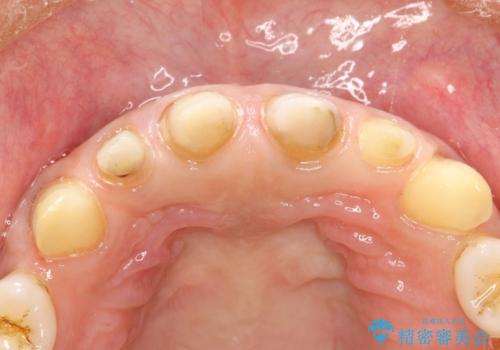

- 昔装着した前歯のかぶせ物を新しくしたいとのことで来院されました。

ご自身の歯とかぶせ物の境目が露出しておりました。

前歯の合計6本をオールセラミッククラウンにする計画としました。